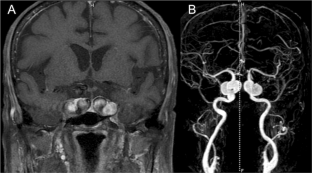

Fig. 1